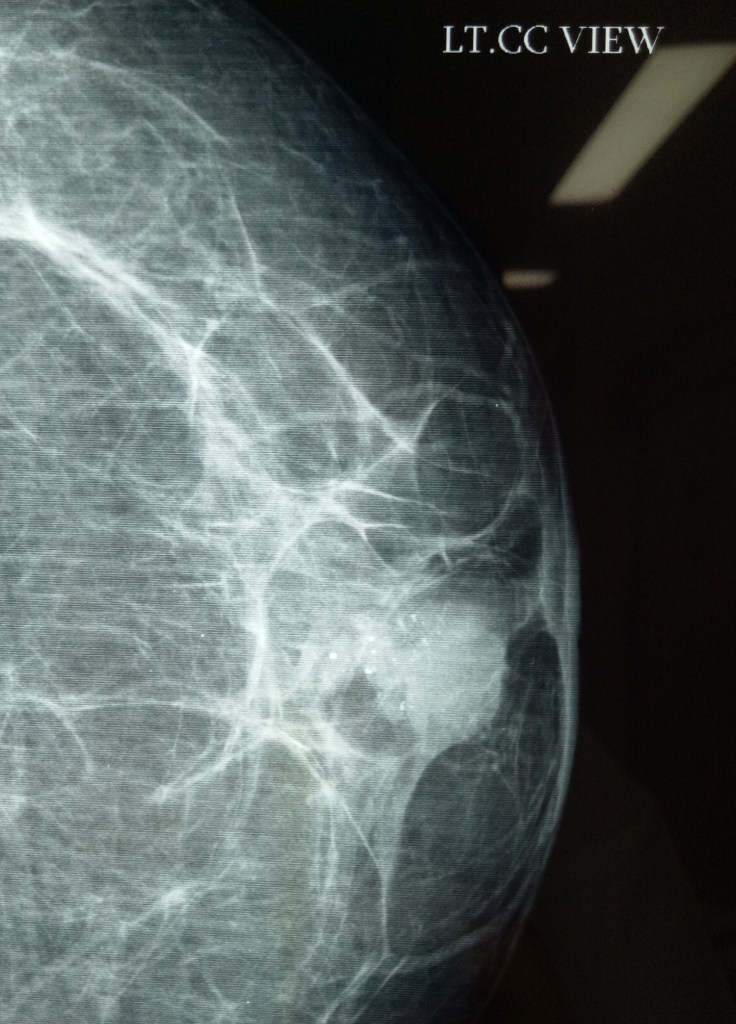

MRM for lobular carcinoma of breast (Dr Jagga’s case). Small tumor (less than 4 cm) and not expected to have metastases in axillary lymph nodes (which were not palpable) actually turned out to have a mass of several enlarged lymph nodes during axillary exploration.

An MRM of the left breast was performed for multicentric lobular carcinoma in a 45 years old female. Dr Jagbir’s case.